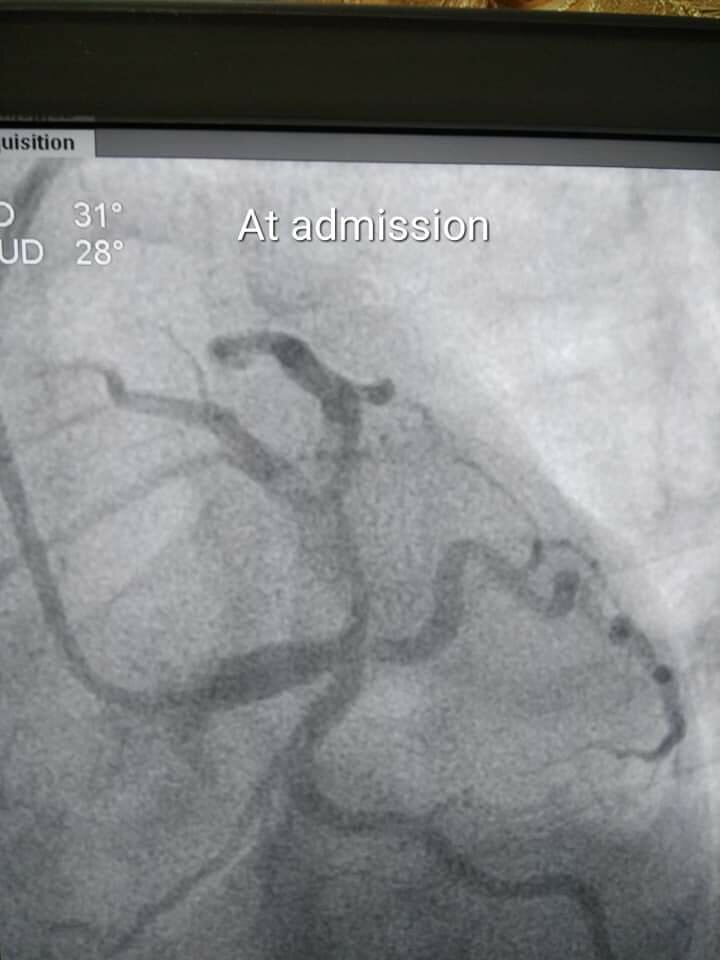

Rapid Life-Saving Primary Angioplasty Case | Dr. Yogesh Jamage

Dr. Yogesh Jamage, leading Consultant Interventional Cardiologist in Miraj–Sangli, successfully managed a high-risk cardiac emergency by perform...

A 28 year male patient diagnosed as hyperacute myocardial infarction (AWMI) referred from periphery for the further management.  Primary angiopla...